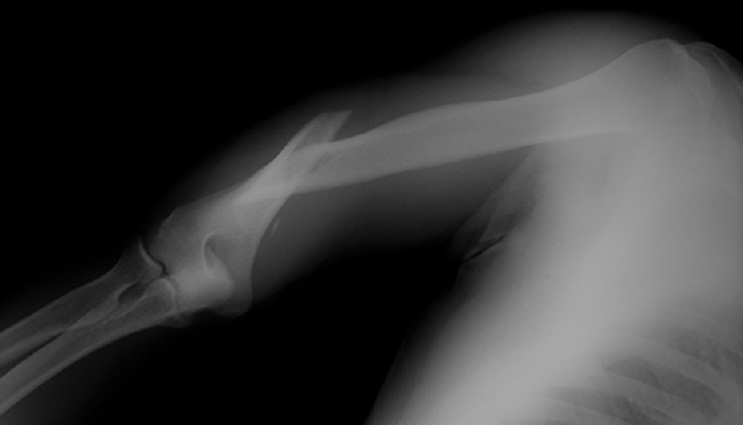

Tulang humerus atau tulang lengan atas adalah tulang panjang yang menghubungkan bahu ke siku. Di sepanjang bagian tengah tulang humerus, tepatnya di bagian terpisah antara otot-otot trisep, terdapat saraf radial yang berjalan melekat dekat tulang.

Karena saraf radial berada sangat dekat dengan tulang humerus dan hanya terlindungi oleh sedikit jaringan lunak, tulang humerus yang patah – terutama akibat trauma energi tinggi (misalnya kecelakaan kendaraan) – dapat dengan mudah menekan atau menarik saraf ini. Akibatnya, fungsi saraf bisa terganggu.

Patah tulang humerus sering kali disertai gejala saraf radial lumpuh (palsi). Bila saraf radial rusak (tertekan, teregang, atau bahkan putus sebagian), pasien akan mengalami kelemahan otot ekstensor sehingga pergelangan tangan dan jari tidak dapat diangkat seperti semula (sering disebut wrist drop atau tangan terkulai), serta mati rasa/baal pada area punggung lengan bawah dan ujung jari tertentu.

Dalam fraktur humerus kasus dewasa, palsi saraf radial terjadi pada sekitar 10–12% kejadian patah humerus, khususnya pada patah melintang atau spiral di bagian tengah bawah tulang yang disebabkan trauma berat.